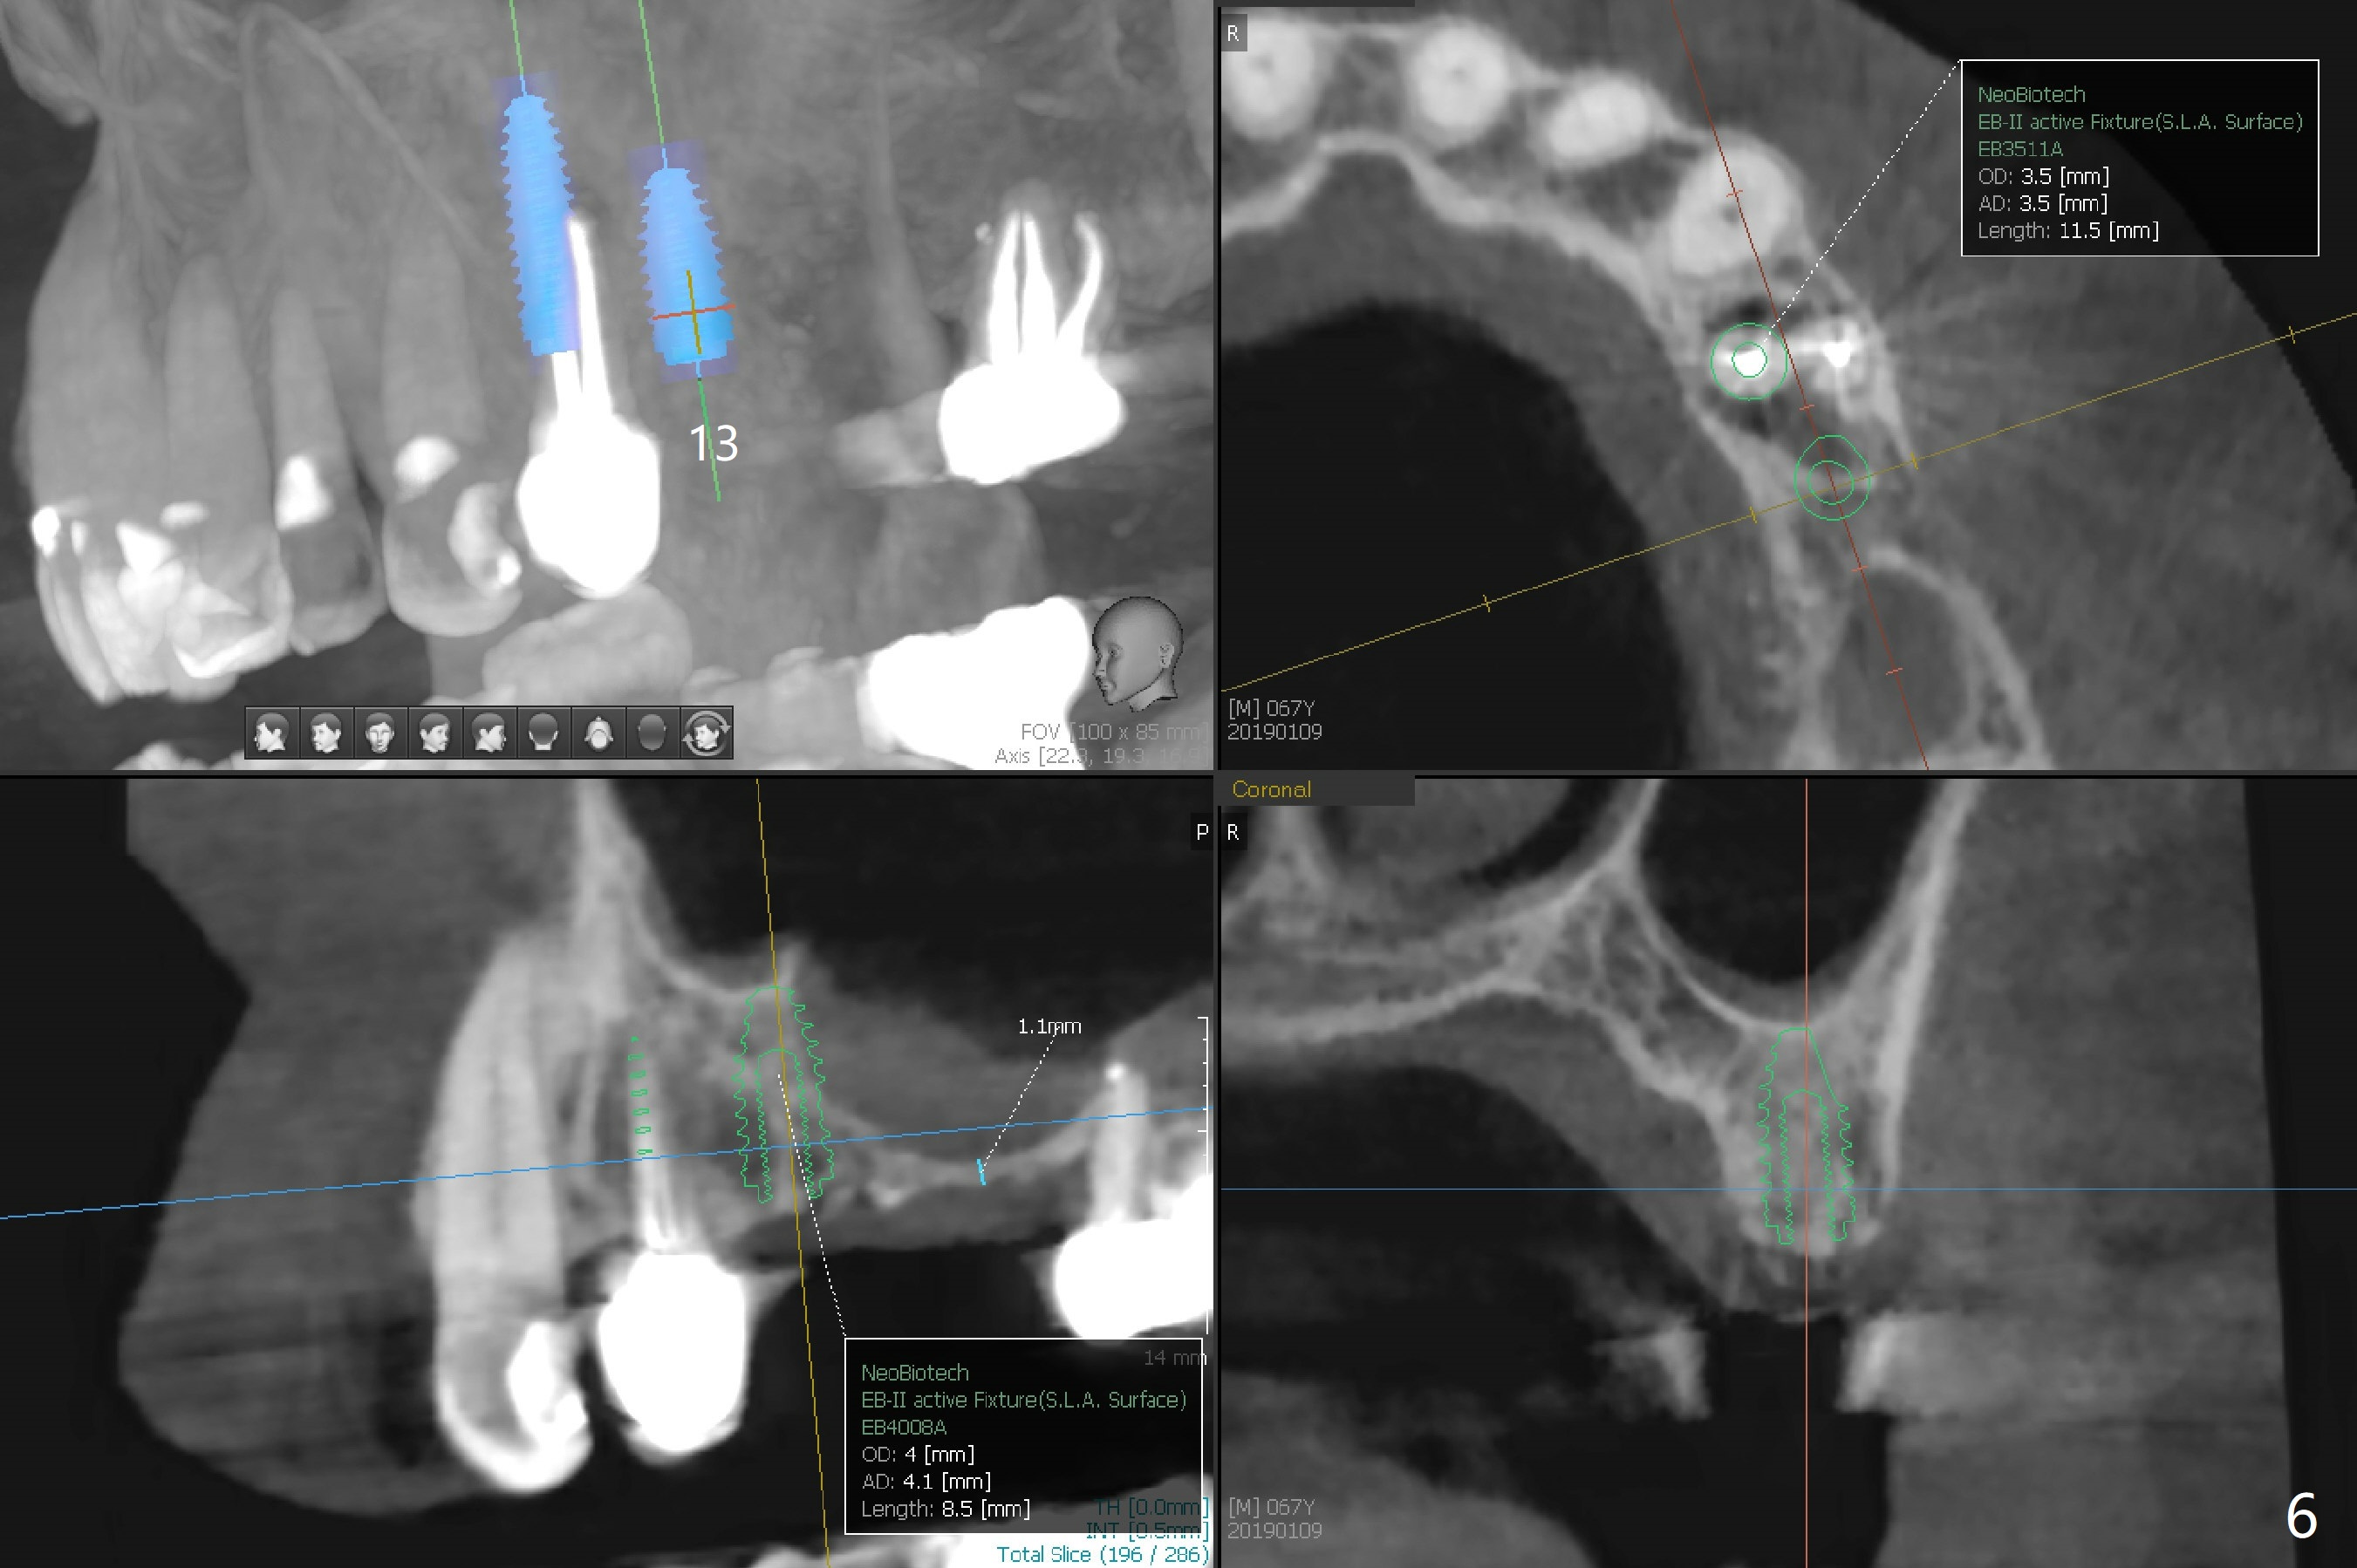

A 63-year-old woman wants to change upper RPD (for #2-4, 13 and 14) to implants because of denture-associated candidiasis. She is afraid of osteoporosis, although the implant at #18 is doing fine almost 3 months post cementation (Fig.1). One way to restore the upper right quadrant is to place 3 short implants (7.3 or 8.5 mm) with guide with simultaneous internal or external sinus lift (Fig.2-4). The tooth #12 appears to have root fracture with periradicular radiolucency (Fig.5); an immediate implant will be placed. While a short implant will be placed at #13, no implant will be placed at #14 because of 1 mm bone (Fig.6). A cantilever FPD will be fabricated in the upper left quadrant. The thick left sinus membrane is a problem as related to a lift?